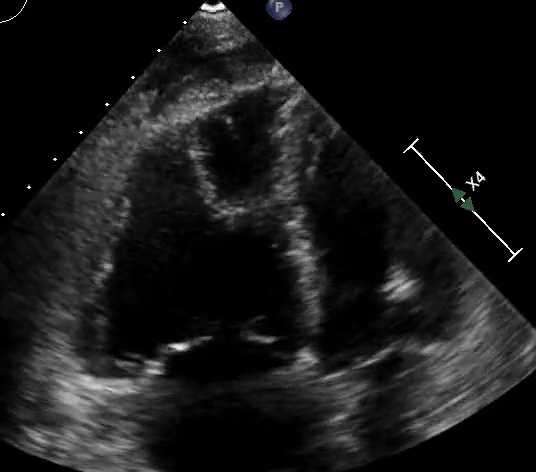

RV assessment can be qualitative or quantitative with attention to RV size, systolic function, pulmonary hemodynamics, or a combination thereof. The visual assessment of RV size and function begins in PLAX, using the “rule of thirds” to uncover the presence of RV dilation (Figure 2). In A4C or the RV-focused view, qualitatively, RV size >2/3 of LV size is considered dilated.7,8 Quantitatively, RV enlargement is present when the RV basal diameter is > 41 mm at the point of the tricuspid valve (TV) insertion to the RV free wall (RVFW) or RV mid-cavity dimension is >35 mm at the level of the open anterior TV leaflet on RVFW.10,11 A RV end-diastolic area to left ventricular end-diastolic area (RVEDA: LVEDA) >0.6 defines moderate RV dilation, while area of (RVEDA: LVEDA) ≥1 suggests severe RV dilation or acute cor-pulmonale, especially when septal dyskinesia is present.10, 12 McConnell’s sign is another qualitative sign of acute cor-pulmonale characterized by dyskinesia of the RVFW with relative sparring of the RV apex (Video 4). It is important to note that the reliability of measurements to assess RV size and function increases with further training and practice.13 (Figure 3)

Figure 3: Quantitative RV dimensions.

RVEDA = right ventricular end-diastolic area, LVEDA = left ventricular end-diastolic area